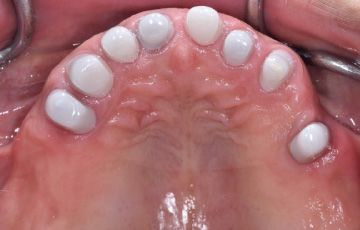

上の歯は「ジルコニア製内冠」を装着し「ジルコニア製テレスコープデンチャー」、

下の歯は天然歯なので歯を削らずに、「ジルコニア製ノンクラスプデンチャー」にしました。

全て金属を使わない入れ歯です。

| 治療内容 | 金属を全く使わない治療を希望していたのでジルコニアセラミックスという素材でテレスコープデンチャーを作製した。 金贋を使わないので身体に侵しく、審美性も噛み心地もよく、イカでもタコでも焼肉でも何でも噛めます。 |